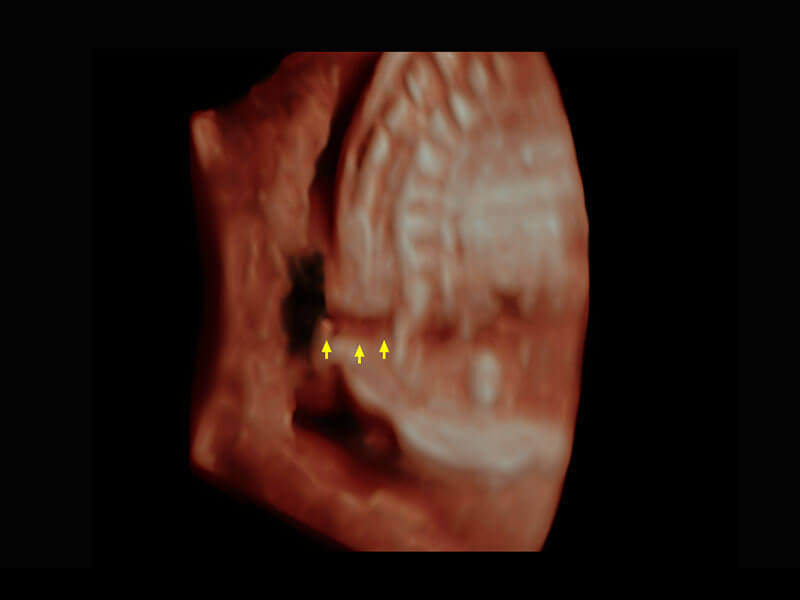

P60為盆底超聲檢查提供應(yīng)用方案,多種腔內(nèi)及腹部容積探頭提供從二維、三維到四維的優(yōu)異圖像品質(zhì),實(shí)時(shí)快速三維容積數(shù)據(jù)獲取,專(zhuān)業(yè)的測(cè)量工具包等人性化設(shè)計(jì),為超聲醫(yī)生診斷提供有力保障。

能夠簡(jiǎn)化盆底檢查的操作流程,可在二維模式及三維成像模式下實(shí)現(xiàn)一鍵自動(dòng)提取出標(biāo)準(zhǔn)切面、自動(dòng)識(shí)別當(dāng)前切面、自動(dòng)測(cè)量,提升盆底檢查的高效性,同時(shí)也能讓青年醫(yī)生快捷的獲得準(zhǔn)確的檢查結(jié)果。

腔內(nèi)三維-宮內(nèi)節(jié)育器

腔內(nèi)三維-光影成像